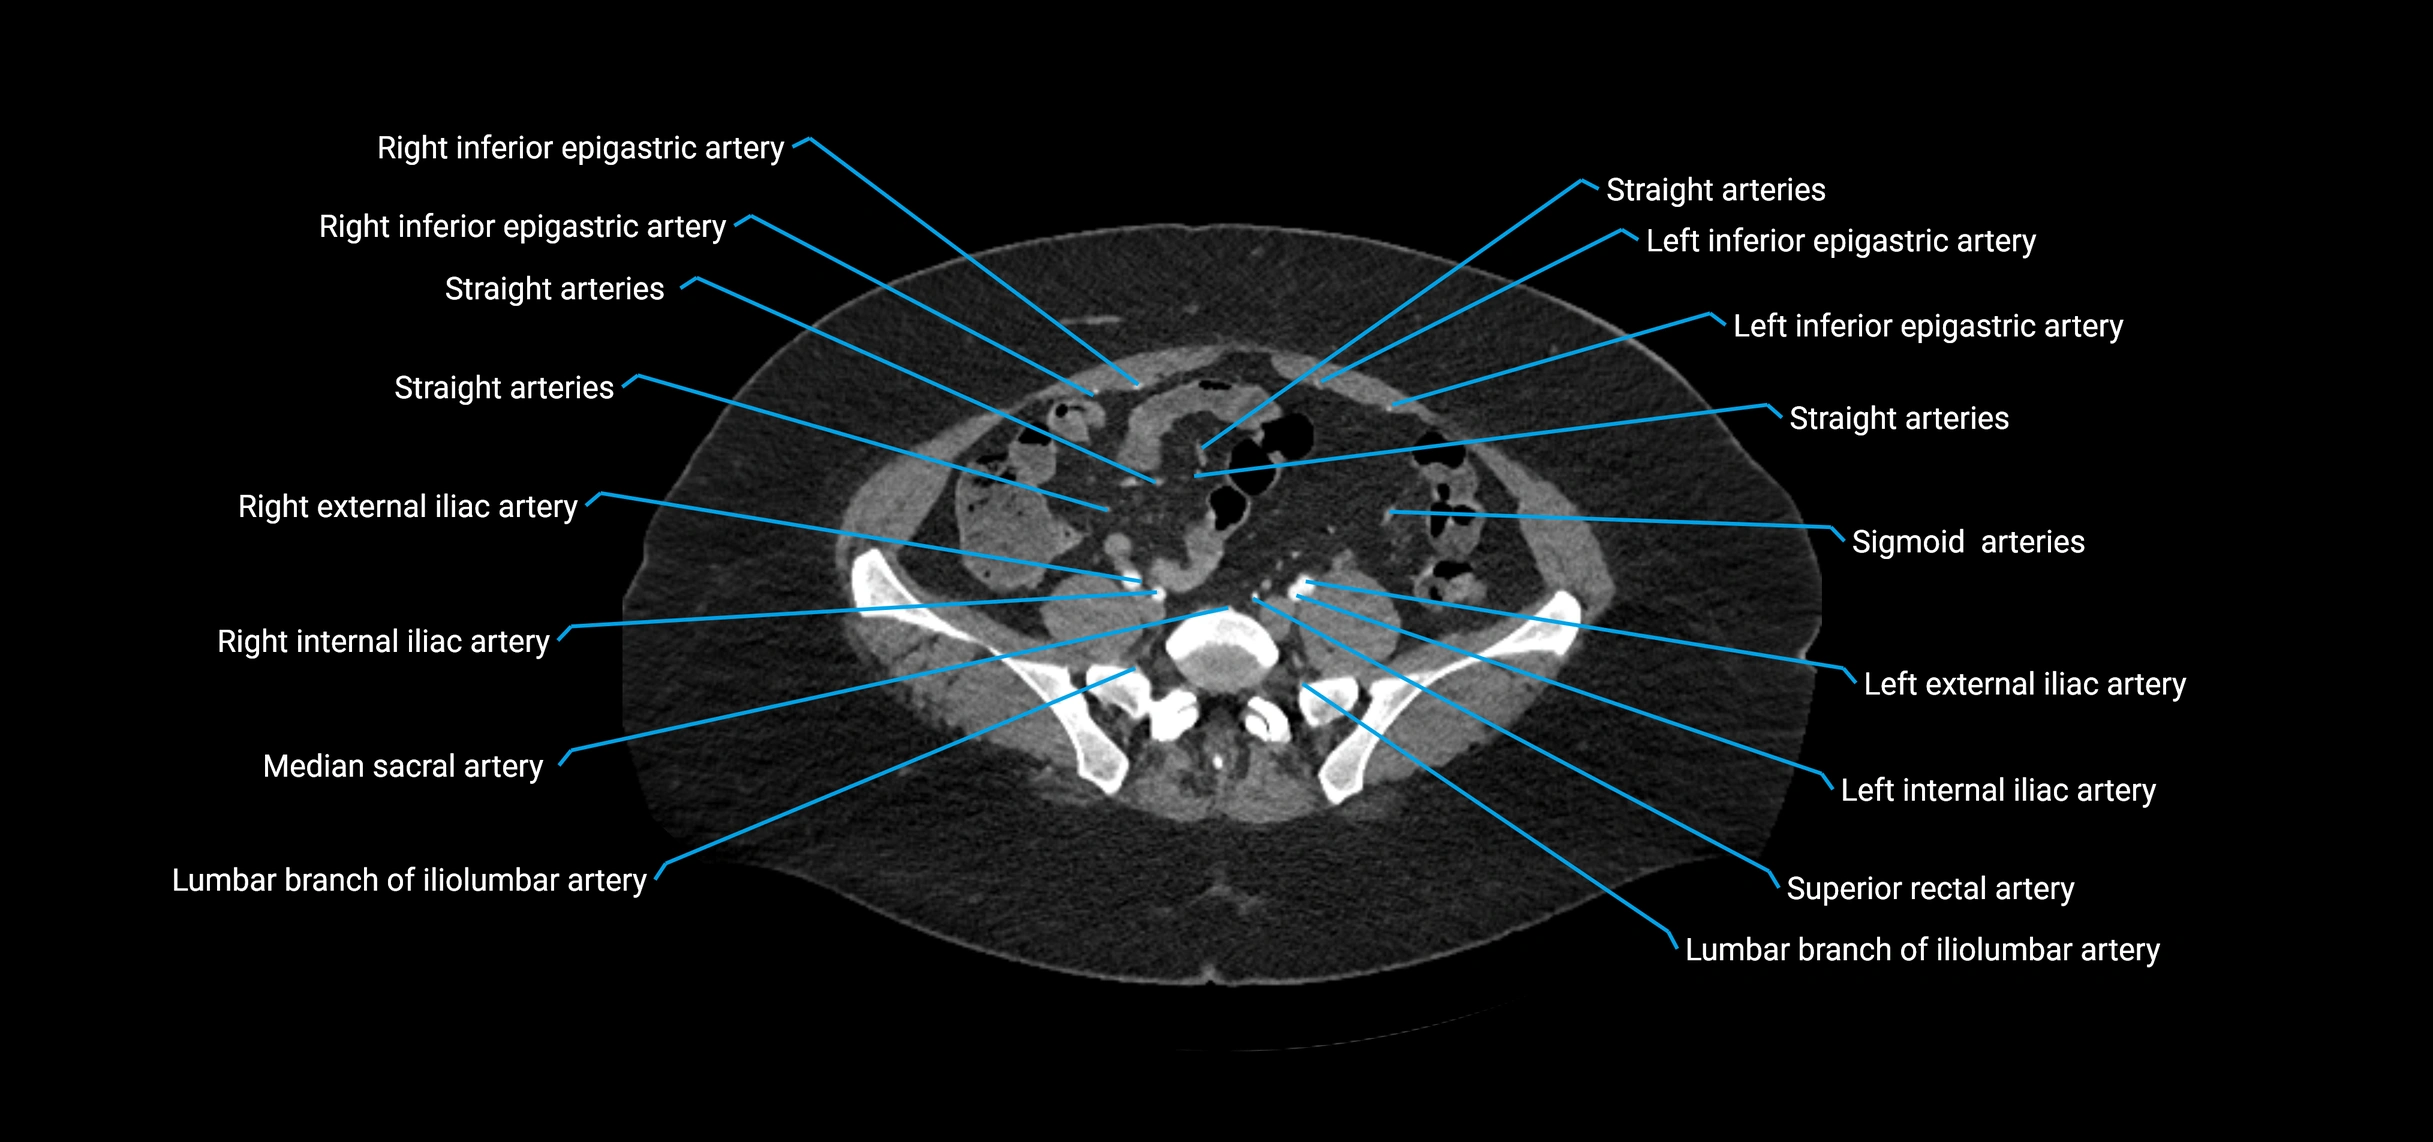

CT images

image

Contrast-enhanced CT (CTA):

• Gold standard for abdominal aortic imaging

• Provides excellent detail of lumen, wall, aneurysm, thrombus, and branch vessels

• Multiplanar and 3D reconstructions help in aneurysm measurement, stent graft planning, and dissection evaluation